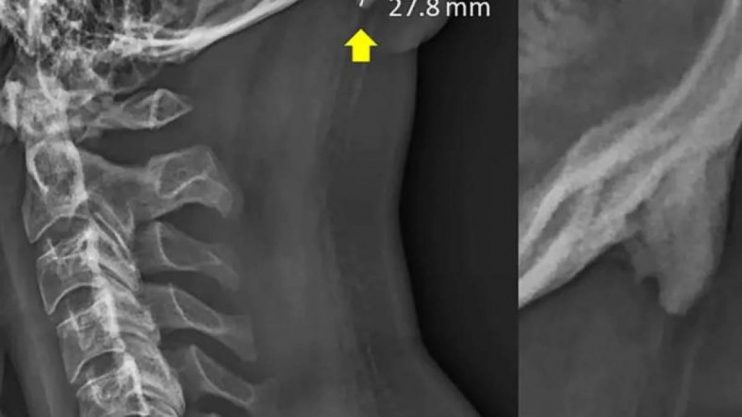

Os jovens estão desenvolvendo chifres na parte de trás de sua cabeça devido à postura incorreta. As causas estão sendo…